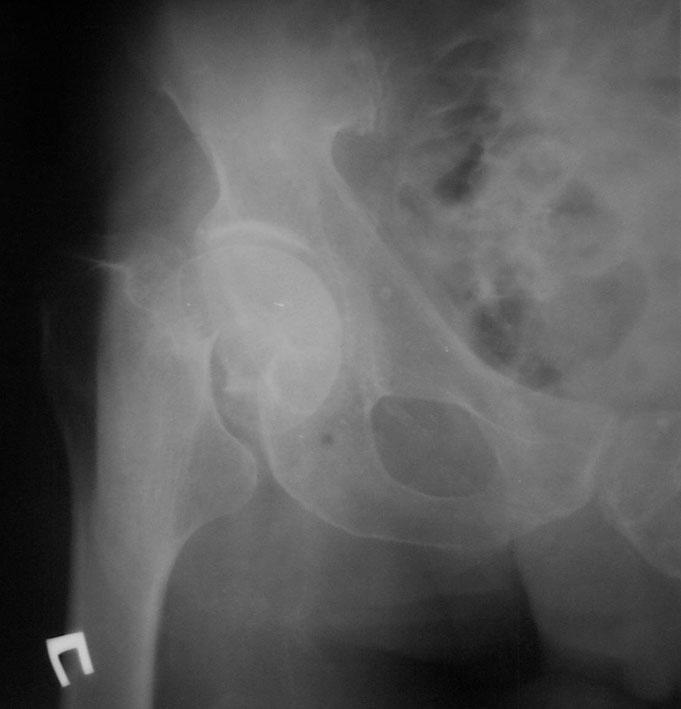

Рентгенограмма тазобедренного сустава в прямой проекции

Доставлен больной Ц. В приемное отделение больницы через 1 час после автотравмы. Жалобы на слабость, головокружение, боли в области правого бедра, невозможность пользоваться конечностью, которая значительно ротирована кнаружи.

П

ри

осмотре: сознание сохранено, но больной

заторможен, кожные покровы бледные, на

лице капли холодного пота. Имеется

угловая деформация верхней трети правого

бедра, конечность фиксирована ремнем

к левой ноге, укорочение

бедра по сравнению со здоровой конечностью

достигает 8 см. Мягкие ткани на уровне

перелома напряжены из-за большого

кровоизлияния. Вследствие укорочения

конечности появились складки кожи над

надколенником, тонус мышц понижен,

выражена патологическая подвижность.

АД 90/70 мм рт. ст., пульс слабый, 120 в

минуту. Иннервация и кровоснабжение

конечностей не нарушено.